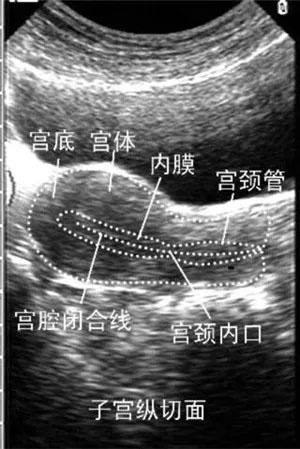

專家指出:導致試管嬰兒治療失敗的原因有很多,其中子宮內膜好壞對于試管嬰兒胚胎移植著床有直接的影響,所以,我們在做俄羅斯試管嬰兒前一定要調養好自己的子宮內膜,多了解一些試管嬰兒知識,這對于提高試管嬰兒的成功率有很大的幫助。